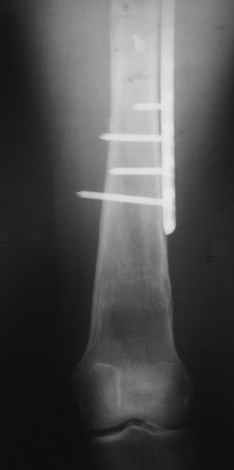

Прошу прощения, со снимками глюк произошел. Высылаю. С уважением Евгений У.

Получилось очень симпатично, мои поздравления. А можно фото конечности без наклеек посмотреть?

И межфрагментарный винт на диафизе - так ли он нужен при выбранном варианте остеосинтеза с относительной стабильностью?

Хотя все-таки закрыто антгерадно заштифтовать тут было вполне можно, и при использовании отечетственного имплантата лечение обошлось бы на порядок дешевле. Опасения коллеги Кульджанова насчет кровоснабжения головки бедра и предстоящих операции в этой области кажуься несколько

преувеличенными - и стержень можно через вертел ввести, да и расстройства кровоснабжения головки, если они случатся после штифтования, не будут длиться вечно.

Но в люом случае, что сделано - то сделано, и сделанное выглядит вполне обнадеживающе, так что еще раз поздравляю коллег с успешным выходом из непростой ситуации.